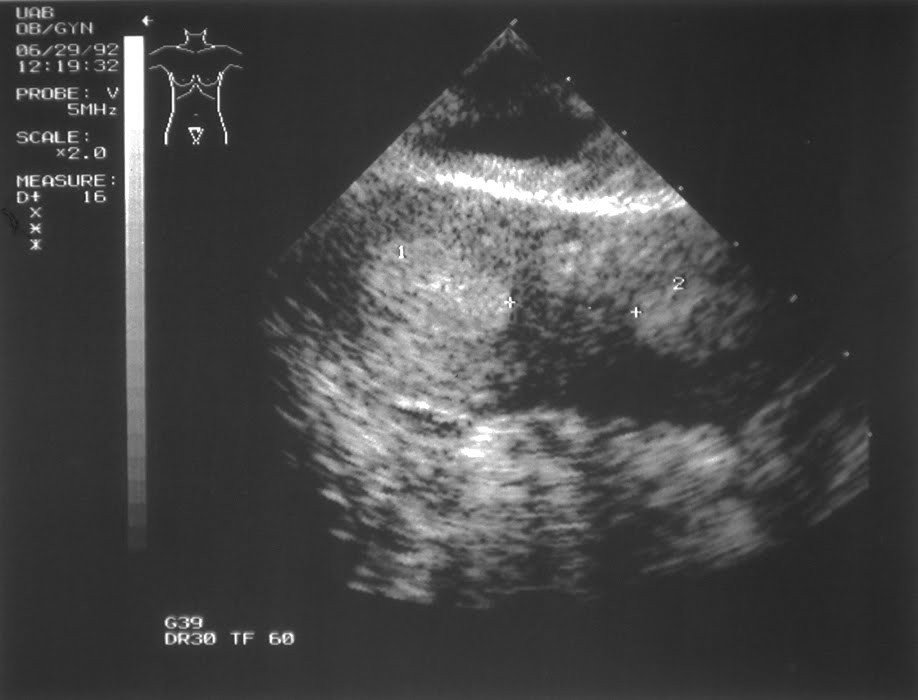

Patient #1 (septate uterus): To the left of the midline, a normal uterus is seen. Arrows mark the endometrium. The cervix is off the screen in the upper left. The top of the uterus is in the lower right.

Moving the probe to view the right side of the uterus, the endometrium reappears.